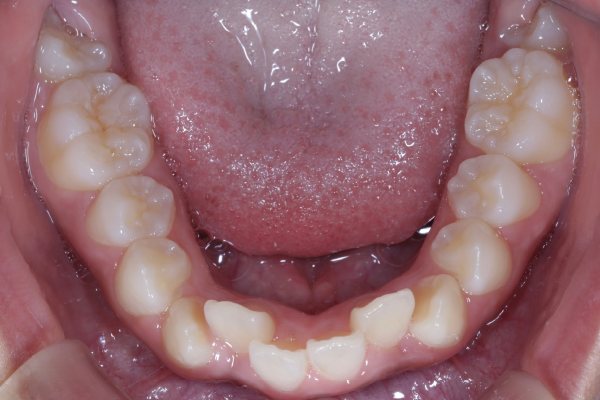

患者様は10代の女性で、前歯を中心とした歯並びのガタつき(叢生)を気にされて来院されました。できるだけ抜歯をせずに矯正治療を行いたいというご希望があり、精密検査を実施しました。

検査の結果、歯列全体のスペースバランスを調整することで、抜歯を行わずに歯並びの改善が可能と判断しました。歯の移動量やコントロール性を考慮し、今回はワイヤー矯正を用いた治療計画をご提案し、患者様にも十分ご理解いただいた上で治療を開始しました。

【矯正治療開始11ヶ月】

11ヶ月経ち歯のガタガタが改善し、歯並びが綺麗になってきています。